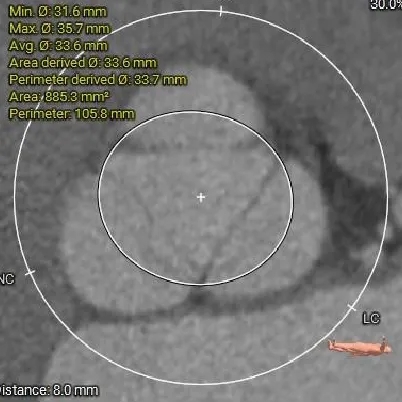

瓣上结构测量

瓣上6mm

30.9mm

瓣上空间逐渐增大,仅瓣上2mm左右可提供锚定